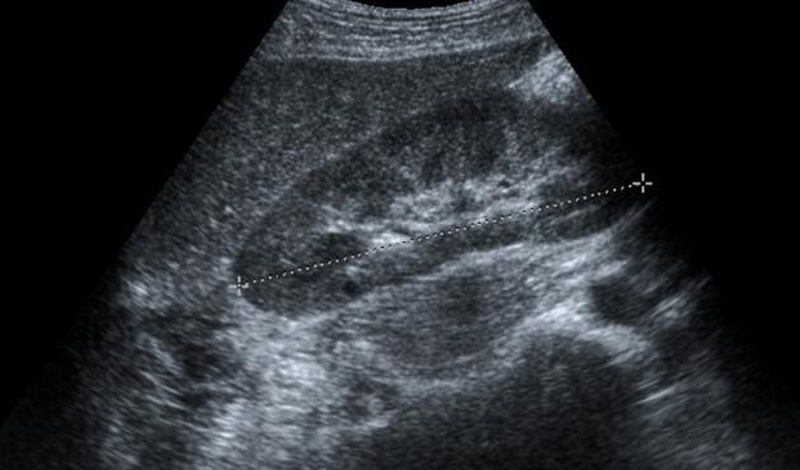

Siêu âm gan là phương pháp chẩn đoán hình ảnh có thể phân định được các thùy, phân thùy và hạ phân thùy của gan, dựa trên mối liên quan với động mạch chủ và tĩnh mạch chủ dưới, tĩnh mạch cửa và tĩnh mạch trên gan. Siêu âm có thể phát hiện nhiều loại thương tổn gan.

Siêu âm gan có thể thấy được các tổn thương của gan, đánh giá được tình trạng gan nhiễm mỡ của người bệnh. Ngoài ra, siêu âm còn phát hiện ra các bệnh áp-xe gan, sán lá gan, nang gan, u gan... thông qua các hình ảnh siêu âm có thể đánh giá được mức độ nặng nhẹ của bệnh tình, từ đó có được phương pháp điều trị phù hợp.

Đối với bệnh nhân viêm gan cấp tính và mãn tính, siêu âm gan có thể thấy được các tổn thương của gan, kích thước gan tăng nhưng hình ảnh nhu mô gan chưa thấy có biến đổi rõ rệt. Ở bệnh gan nhiễm mỡ, khi siêu âm sẽ thấy một phần hay toàn bộ nhu mô gan sáng, từ đó có thể đánh giá được tình trạng gan nhiễm mỡ của người bệnh.

Đối với xơ gan, chẩn đoán siêu âm dựa vào kích thước gan và nhu mô gan. Kích thước gan lúc đầu tăng lên, về sau ở giai đoạn muộn gan teo nhỏ. Ở giai đoạn muộn của xơ gan, siêu âm còn có thể thấy gan có hình nốt nhỏ và vừa đường kính dưới 1cm. Ngoài ra, siêu âm còn có thể phát hiện các hậu quả của xơ gan như cổ trướng, giãn tĩnh mạch, lách to.

Với người bị ung thư gan, việc siêu âm rất quan trọng. Ung thư gan có thể phát triển trên nhu mô gan lành nhưng đa số (63 – 83%) xuất hiện trên gan xơ do rượu hoặc do hậu quả của viêm gan virus. Ở người lớn, đại đa số là ung thư biểu mô tế bào gan, ở trẻ em nhất là dưới 2 tuổi thường là ung thư phôi bào gan.

Ngoài ra, siêu âm còn phát hiện ra các bệnh áp-xe gan, sán lá gan, nang gan, các khối u lành tính, các tổn thương di căn, các bệnh lý đường mật trong gan thông qua các hình ảnh siêu âm có thể đánh giá được mức độ nặng nhẹ của bệnh tình, từ đó có được phương pháp điều trị phù hợp.